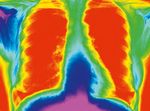

N

egli ultimi anni, l’ecografia clinica o Point-of-care                                     a scopo diagnostico, per monitoraggio o guida a

(POCUS) si è estesa da semplice test di screening                                         procedure 1. La crescente necessità di avere diagnosi

utilizzato prevalentemente nelle urgenze a                                                sempre più rapide e di utilizzare razionalmente le

strumento utilizzato da quasi tutte le branche mediche                                          risorse sanitarie ha determinato che la POCUS sia stata

Non Commercial (CC BY-NC 4.0)”, che consente agli utenti di distribuire, rielaborare,             Da sempre il torace per la sua conformazione è stato

adattare, utilizzare i contenuti pubblicati per scopi non commerciali; consente inoltre

di realizzare prodotti derivati comunque e sempre solo a fini non commerciali, citando        considerato inaccessibile dal punto di vista ecografico. La

propriamente fonte e crediti di copyright e indicando con chiarezza eventuali modifiche

apportate ai testi originali.                                                                 presenza della cassa toracica ossea e dell’aria contenuta

We people | 1 - 2019   13

nei polmoni, che attenuano maggiormente gli ultrasuoni          valutazione d’organo o di patologia, come avviene nella

rispetto ad altri tessuti, hanno fatto sì che le indicazioni    Radiologia convenzionale 8.

allo studio ecografico del torace fossero limitate alla             Alla sua rapidità di esecuzione, facilità di

valutazione del cuore e dei grossi vasi 3,4 e che, per quanto   apprendimento della tecnica, ripetibilità, al basso costo

riguarda il polmone, lo studio fosse limitato a patologie       e alla non invasività si associa anche la totale assenza di

pleuriche come tumori o versamenti 5.                           radiazioni.

esame clinico senza un’accurata auscultazione del torace,       oltre alla già menzionata capacità di ridurre la radio-

che ha un impatto fondamentale sulla valutazione                esposizione da esami radiografici. Il minor spessore e

globale, non solo del sistema respiratorio, ma anche dello      diametro del torace del neonato o bambino rendono

stato emodinamico.                                              l’esecuzione dell’esame più semplice rispetto all’adulto

Ciò ha stimolato la ricerca ad analizzare e interpretare    e la rappresentazione dell’immagine migliore 7. La

gli artefatti creati dall’ecografia toracica, riconsiderando    tecnica di esame risulta più semplice rispetto ad altri

le ragioni che sono state sempre ritenute limitazioni per       esami ecografici e necessita di una breve curva di

effettuarla 2,7.                                                apprendimento.

Risale alla metà del secolo scorso l’intuizione che gli         Tuttavia, l’ecografia toracica ha dei limiti che vanno

artefatti ecografici creati dall’aria presente nel polmone,     conosciuti per permetterne un corretto utilizzo 2,7.

se ben interpretati, potessero fornirci significative               All’ecografia risultano visibili solo le alterazioni

informazioni qualitative e quantitative sullo stato             parenchimali che raggiungono la pleura 1 (sia

dell’organo. Il polmone normalmente areato determina,           direttamente sia con liquido interposto) e solo il 60‑70%

infatti, una completa riflessione degli ultrasuoni, facendo     della superficie pleurica è esplorabile 10. La presenza

sì che il parenchima sottostante risulti non visibile ma        di eventuale enfisema sottocutaneo può impedire la

sostituito da caratteristici artefatti. La comprensione delle   propagazione degli ultrasuoni e la ricostruzione degli

caratteristiche degli artefatti e la descrizione di pattern     artefatti. Infine, non è possibile spesso discriminare

specifici di determinate patologie hanno portato alla           se un consolidamento sotto-pleurico possa essere

crescita e allo sviluppo dell’ecografia toracica nell’ambito    un addensamento di natura infettiva (polmonite)

della POCUS 2.                                                  o un’atelettasia esclusivamente con le immagini